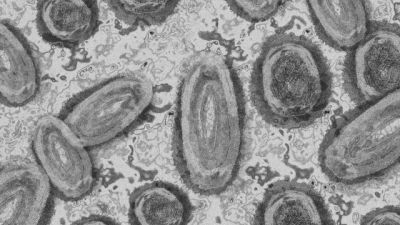

Първи случай на маймунска шарка в Румъния. Как се предава инфекцията?

Първи случай на маймунска шарка беше потвърден в Румъния, съобщи Аджерпрес, позовавайки се на Министерството на здравеопазването на страната. Към момента в ЕС няма одобрена ваксина срещу вируса на маймунската вариола.

Става въпрос за 26-годишен мъж от Букурещ. Той е бил диагностициран с болестта след лабораторни изследвания.

Пациентът се е разболял преди четири дни, а снощи се е явил в болница. "Мъжът е в добро състояние. Получава симптоматично лечение и се намира в изолация. От анамнезата става ясно, че партньорът на заразеното лице е пътувал в последно време в няколко страни в Европа, където съществуват редица случаи на инфекция с маймунска шарка", посочват от министерството.

Инфекцията не се предава лесно от човек на човек. Заразяването се случва при близък контакт с инфекциозен материал от кожните лезии на инфектиран човек, както и чрез респираторни капчици при продължителен контакт лице в лице. Възможно е вирусът да бъде предаден и при използване на общо спално бельо, дрехи и тоалетни принадлежности, където оцелява за дълго време. Моментната епидемична ситуация най-вероятно се свързва с предаване по сексуален път сред мъже, които правят секс с мъже (MSM), но е възможно разпространение и сред членовете на едно домакинство. Безразборните сексуални контакти се оценяват като високорисков фактор за разпространение на вируса.

Повечето случаи на инфекцията при дадения епидемичен взрив в Европа протичат леко. В риск от тежко заболяване са малки деца, бременни и имунокомпрометирани пациенти. Тъй като случаите са все още малко на брой, профилът на тежест на заболяването не може да бъде надеждно оценен.

Към момента в ЕС няма одобрена ваксина срещу вируса на маймунската вариола, но ваксината срещу едра шарка показва ефективност срещу маймунската вариола. Европейският център за профилактика и контрол на заболяванията препоръчва биопродуктът да се използва като средство за пост-експозиционна профилактика. Експертите оценяват необходимостта от имунизация на медицинския персонал, ангажиран в грижата за заболелите от вируса.